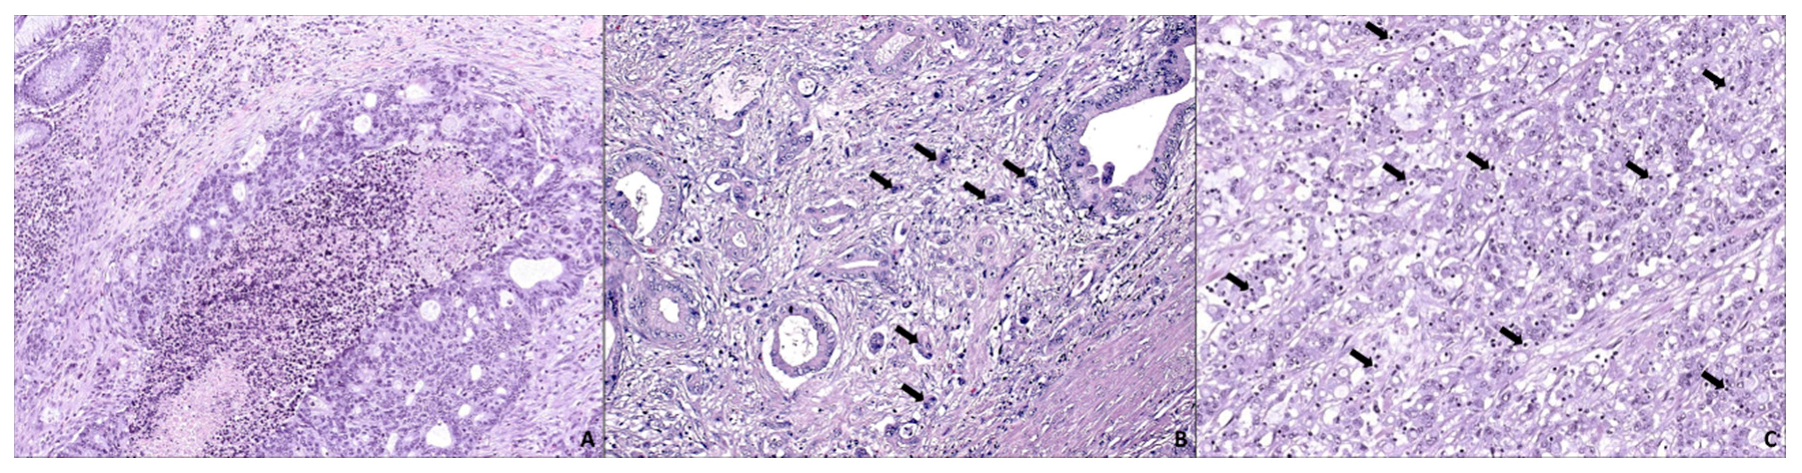

- Tuomisto, A.; García-solano, J.; Sirniö, P.; Väyrynen, J. HIF-1 α expression and high microvessel density are characteristic features in serrated colorectal cancer. Virchows Arch. Int. J. Pathol. 2016, 469, 395–404. [Google Scholar] [CrossRef] [PubMed]